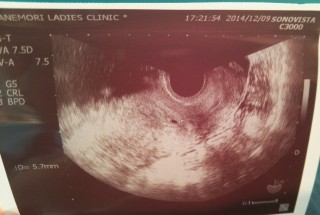

胚盤胞移植での妊娠です。 胎嚢は5.7mmでした。少し小さめで不安ですが、この子を信じます!